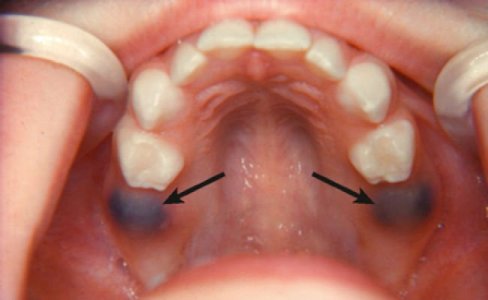

Гематома — это скопление крови в мягких тканях. Внешне гематома похожа на простой кровоподтек, цвет повреждения которого может варьироваться от красноватого до синюшного и желтого. Большие гематомы могут вызывать воспалительный процесс, сопровождающийся болезненными ощущениями, опуханием, общим недомоганием и, в некоторых случаях, повышенной температурой тела. В зависимости от типа образования и причины его появления лечение может включать в себя медикаментозную терапию, наложение компресса для сужения просвета сосудов, физиотерапевтические процедуры, хирургическое вмешательство.